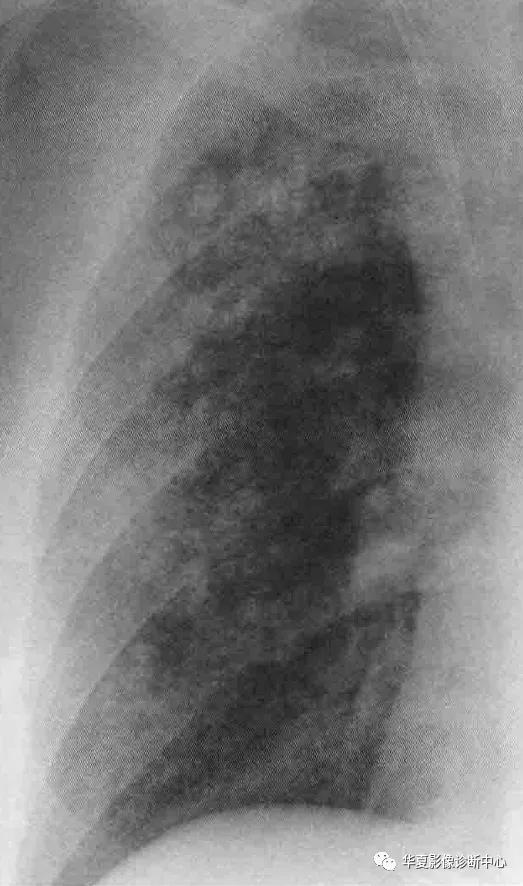

影像学表现:X线特征性表现为爽哦片状实变内隐约可见结节,50%病例实变分布于肺门周围,其余病例随机分布或主要分布于周边或基底部,有时肺实质受累不对称或单侧受累。CT主要典型表现为双侧磨玻璃影(尤其肺背侧部分),几乎均匀累及全非,也可以下肺分布为主,大部分病例可见碎石铺路征,即一个细线形成的直径3-10mm多边形叠加在磨玻璃影上,反应了肺间质水肿的存在或小叶间隔毗邻的空腔内脂蛋白样物质的聚集;正常和异常肺实质边界锐利清楚。